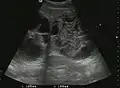

Liver abscess

Liver abscess have heteromorphic ultrasound appearance, the most typical being that of a mass with irregular shapes, fringed, with fluid or semifluid content, with or without air inside. Doppler examination shows the lack of vessels within the lesion. CEUS exploration shows hyperenhancement during arterial phase close to the lesion, this being suggestive of a liver parenchymal hyperemia. During venous and sinusoidal phase the pattern is hypoechoic, and the central fluid is contrast enhanced. CEUS examination is useful because it confirms the clinical suspicion of abscess. In addition, it allows for an accurate measurement of the collection size and an indication regarding its topography inside the liver (lobe, segment).